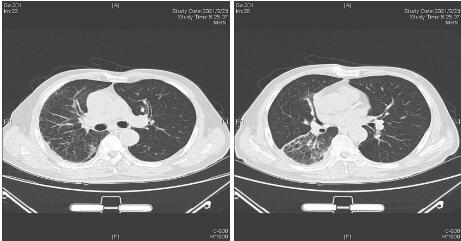

患者经过近1周治疗,临床症状较前好转,心衰纠正,炎症指标明显下降,于1月31日体温正常后转普通病房。感染方面美平降级为头孢派酮舒巴坦,继续多西环素治疗。2月2日外送标本DNA测序鉴定为Balneatrix alpica,即阿尔卑斯浴者菌。后续患者出现胸膜炎性胸痛,间断气促,复查肺部CT提示右侧胸腔积液量增多,给予穿刺引流,胸水外送经DNA鉴定报高山巴氏发菌,即Balneatrix alpica,至此患者感染的病原菌明确,考虑此菌为少见菌,对抗菌药物敏感性较高,后续抗生素方案降解为左氧氟沙星500 mg/d,经治疗3周后患者出院,后期随访追踪无不适。

| 图 2 2月1日复查胸部CT平扫 |